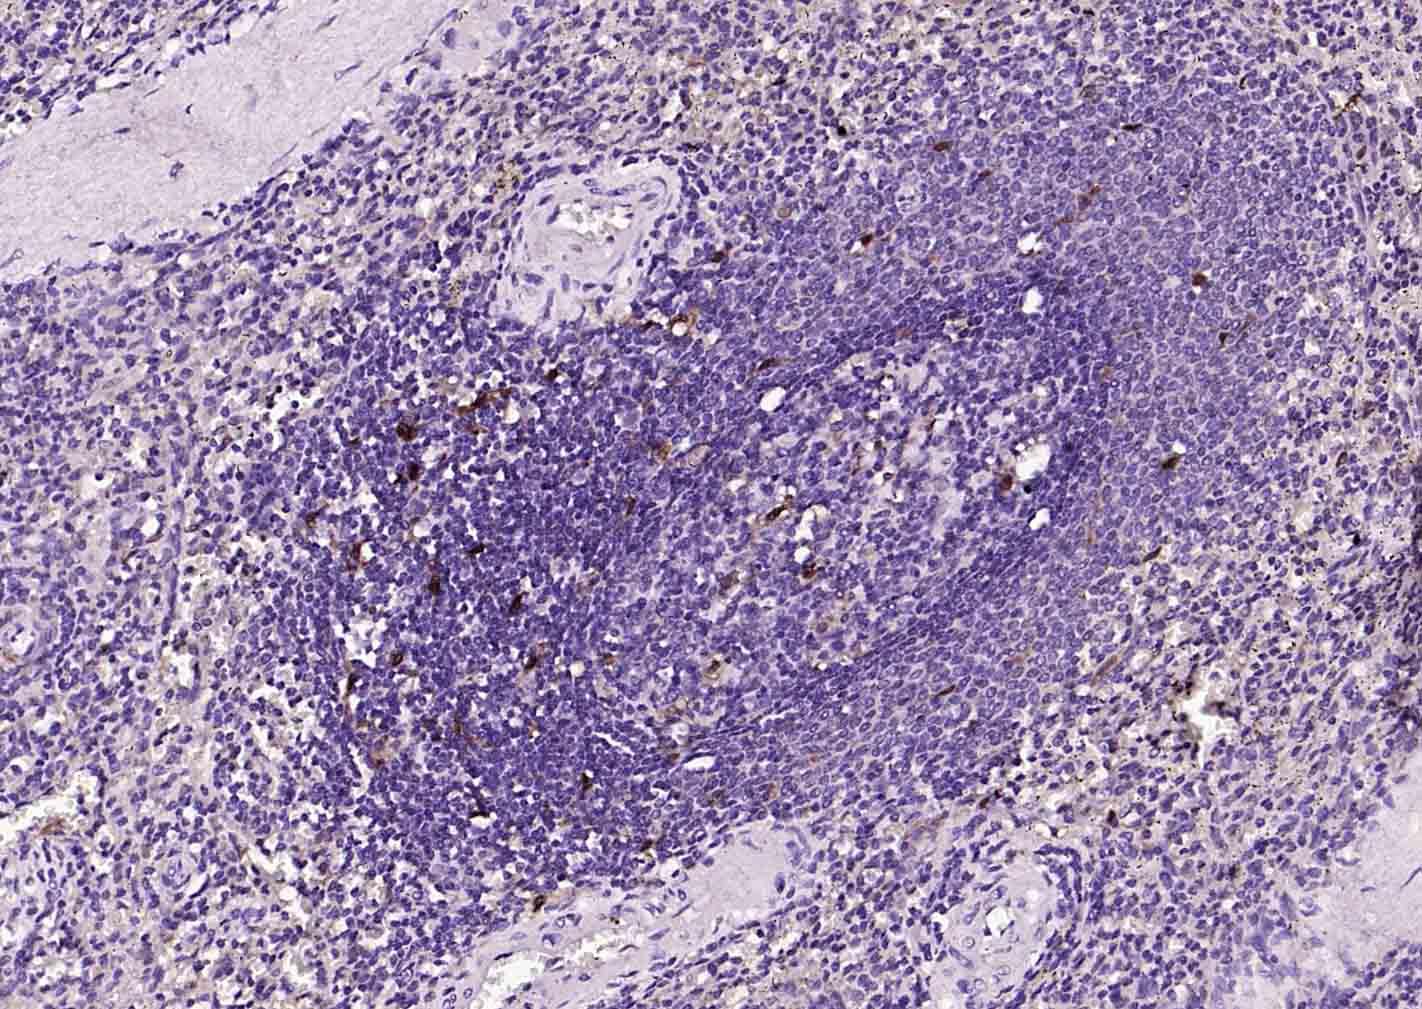

Paraformaldehyde-fixed, paraffin embedded (human spleen); Antigen retrieval by boiling in sodium citrate buffer (pH6.0) for 15min; Block endogenous peroxidase by 3% hydrogen peroxide for 20 minutes; Blocking buffer (normal goat serum) at 37°C for 30min; Incubation with (IL18 ) Monoclonal Antibody, Unconjugated (bsm-54805R) at 1:300 overnight at 4°C, followed by operating according to SP Kit(Rabbit) (sp-0023)instructionsand DAB staining.

Paraformaldehyde-fixed, paraffin embedded (human tonsil); Antigen retrieval by boiling in sodium citrate buffer (pH6.0) for 15min; Block endogenous peroxidase by 3% hydrogen peroxide for 20 minutes; Blocking buffer (normal goat serum) at 37°C for 30min; Incubation with (IL18) Monoclonal Antibody, Unconjugated (bsm-54805R) at 1:200 overnight at 4°C, followed by operating according to SP Kit(Rabbit) (sp-0023) instructionsand DAB staining.